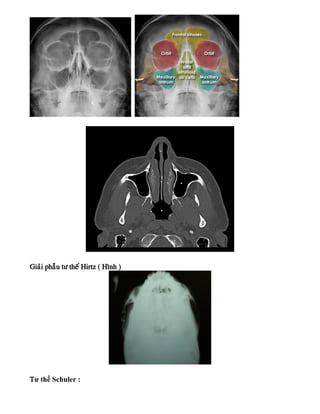

Hay chæ ñònh chuïp trong beänh vieän vaø tö theá hay khaûo saùt laø Blondeau vaø Hirtz ñeå

quan saùt xoang haøm – xoang traùn – xoang saøng , ngoaøi ra coøn quang saùt heä xöông lieân

quan.

Gæai phaãu tö theá Blondeau ( Hình )

Giaûi phaãu tö theá Hirtz ( Hình )

Tư thế Schuler :